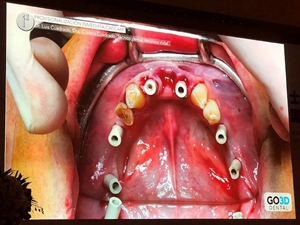

第三,植入種植體,安裝掃描桿,并再次進(jìn)行口內(nèi)掃描,獲取數(shù)字化植入信息。

接下來(lái),Dr. Luis Cuadrado將全數(shù)字化修復(fù)流程同CT導(dǎo)板引導(dǎo)種植流程相結(jié)合,實(shí)現(xiàn)術(shù)前即可在軟件上制作數(shù)字化修復(fù)體。通過(guò)在計(jì)算機(jī)設(shè)計(jì)時(shí)將基臺(tái)數(shù)據(jù)(角度、高度信息等)信息轉(zhuǎn)移到導(dǎo)板上,使植入后修復(fù)更符合美學(xué)、功能等標(biāo)準(zhǔn)。